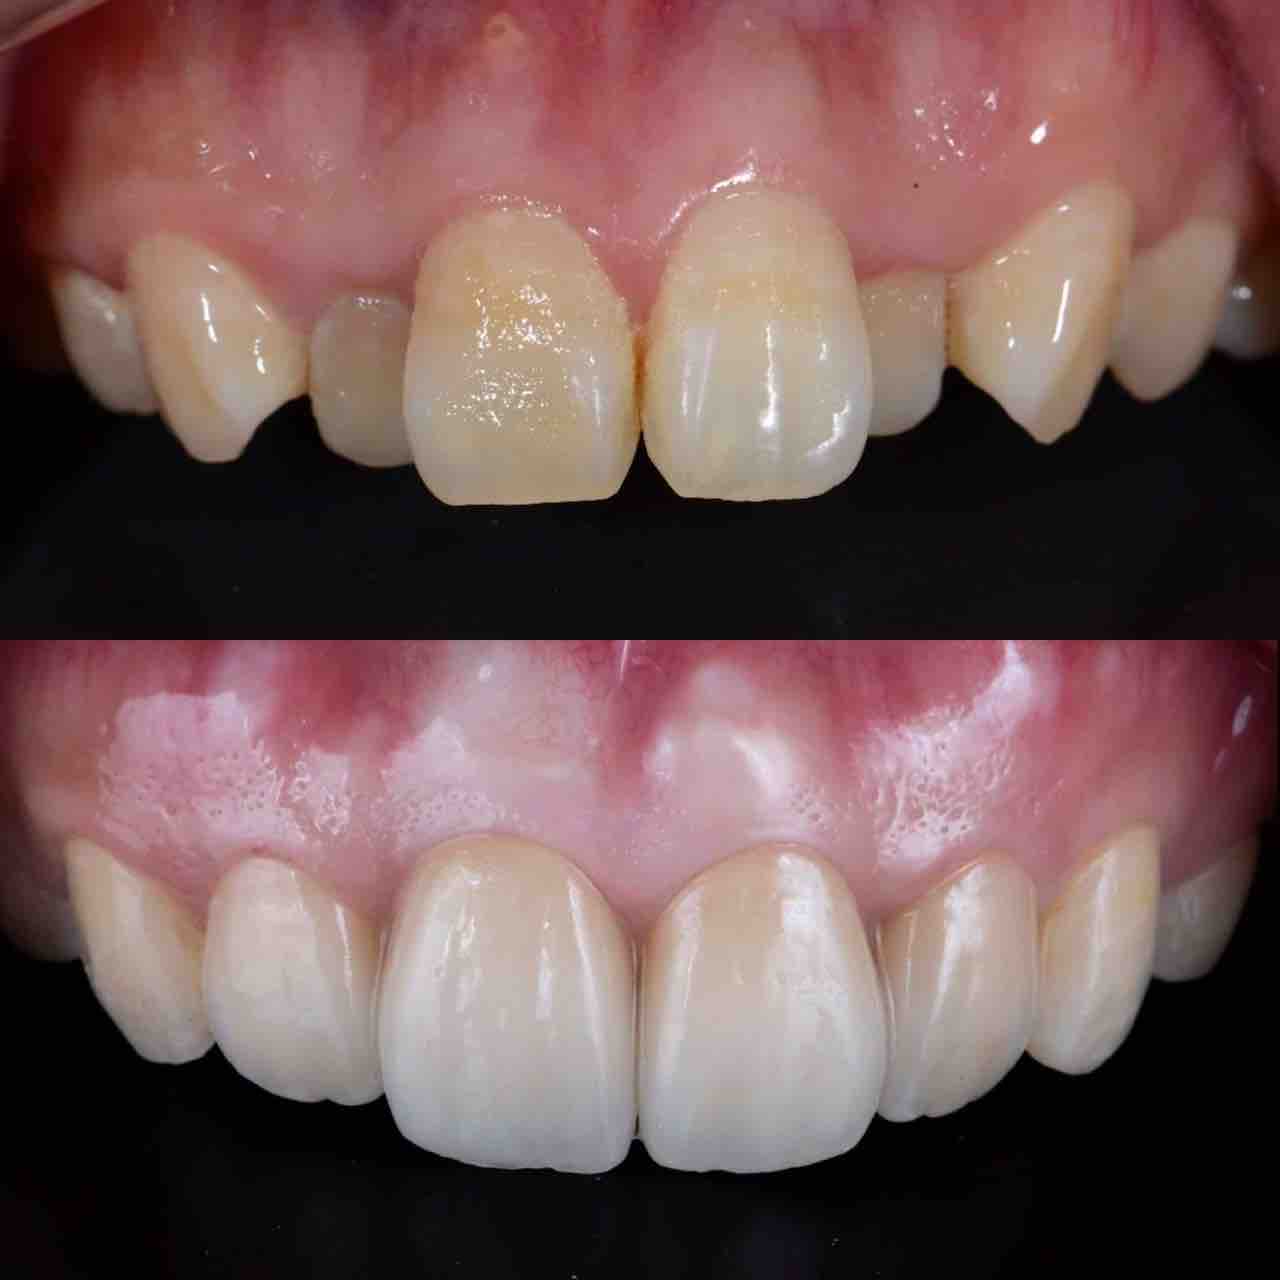

¥¤¥ó¥¹¥¿¥°¥é¥à¤ËºÜ¤»¤Æ¤¤¤ëÅö±¡¤Î¾ÉÎã¤Ç¤¹